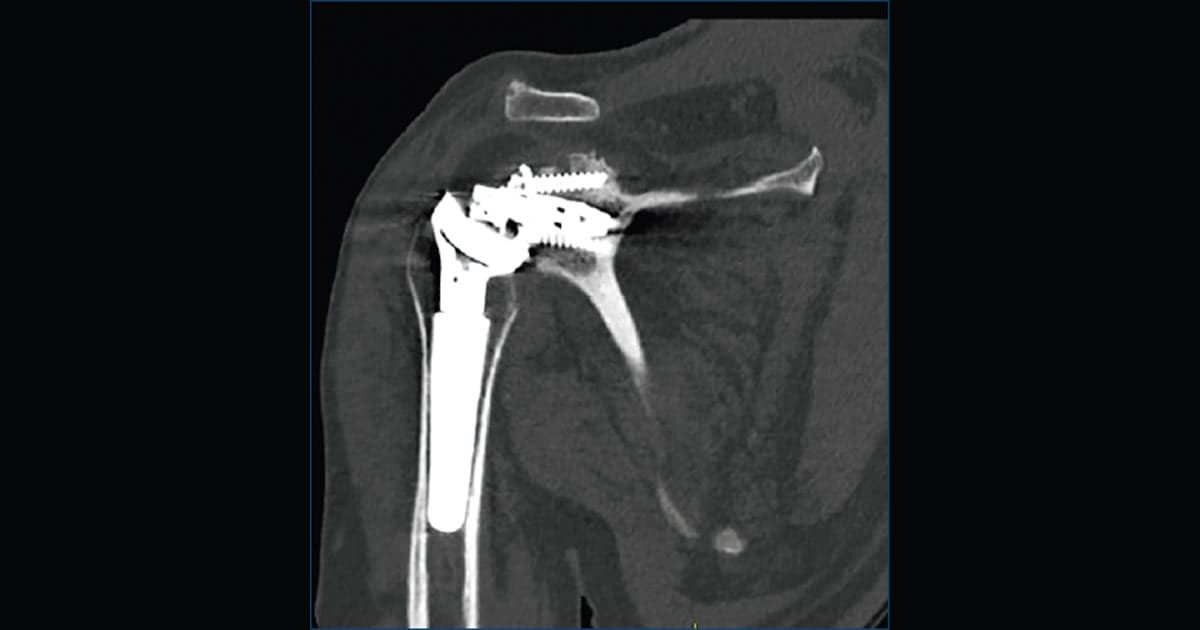

• radiografie o TC suggestive di mobilizzazione della componente glenoidea.

Radiografie comparative e TC svolgono un ruolo fondamentale nel valutare la posizione della glenosfera e il grado di allentamento della componente.